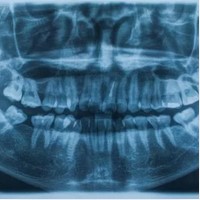

Digital X-RayDigital X-Ray

At Aiko Dental & Implant Center, we're committed to providing the most advanced and accurate diagnostic tools to ensure your optimal oral health. Our digital X-ray technology is a game-changer in detecting and treating dental issues early on.